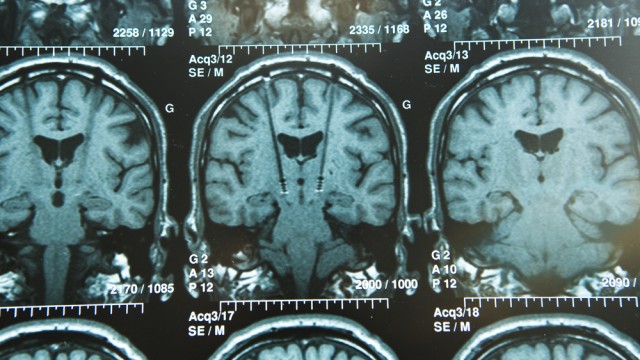

אפליקציה בטלפון הנייד תוכל מעתה לאפשר לחולה פרקינסון ולרופאיו לשלוט בתסמיני המחלה. מערכת לגירוי מוחי עמוק בחולה פרקינסון, המיועדת להפחתת תסמיני המחלה ונשלטת באמצעות אפליקציה בנייד, הושתלה לראשונה במרכז הרפואי שיבא בתל השומר.

במסגרת ההליך שבוצע במטופל, הושתלה בשלב ראשון אלקטרודה באזור הנדרש במוח. לאחר מכן הושתל קוצב מתחת לעור בקדמת בית החזה, שתפקידו לשגר לאלקטרודה אותות חשמליים באמצעות כבל תת עורי שמחבר ביניהם. כיוון עוצמת האותות נעשה על ידי הרופא באמצעות שלט, בהתאם לתכנית הטיפול. השתלת המערכת בוצעה בהרדמה מלאה. המרדימים, ד"ר אאורליה גלאובר וד"ר תומר ניר, ביצעו את ההרדמה באופן שמאפשר פעילות מוחית מלאה למרות שהמטופל לא הרגיש בדבר. לדברי ד"ר זיבלי, המטופל התאושש מהניתוח וכבר חל שיפור בתסמינים.